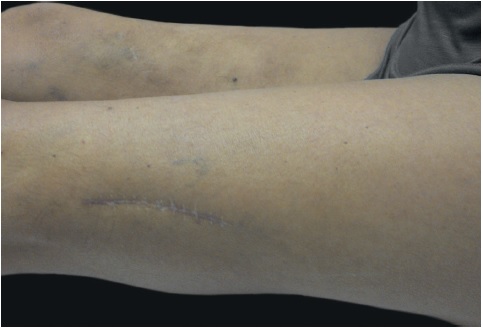

Relata-se o caso de paciente do sexo feminino, 50 anos, parda, pouco assídua, que se apresentou à consulta na Clínica de Dermatologia de serviço universitário no Rio de Janeiro, Brasil, em novembro de 2001, com placa eritêmato-infiltrada, indurada, medindo 25cm de comprimento, com aumento de temperatura e localizada na face anterior da coxa direita (Figura 1), tendo surgido há quatro anos. Com a hipótese de paniculite, foi realizada biópsia, cujo estudo anatomopatológico revelou fase crônica de EN. No seguimento ambulatorial, as condições possivelmente associadas (tricomoníase, onicomicose, paroníquia, hidradenite e escabiose) foram adequadamente tratadas. Os resultados de exames laboratoriais − hemograma, bioquímica, função tireoidiana, sorologias para hepatites B e C, VDRL, anti-HIV, ASLO, alfa-1-antitripsina, sedimento urinário, parasitológico de fezes – e RX de tórax foram normais. Foram utilizados anti-inflamatórios não hormonais, solução saturada de iodeto de potássio oral (atingidas apenas 15 gotas/dia por intolerância gastrointestinal), iodeto de potássio em creme e corticoterapia sistêmica nos períodos de maior inflamação, sem mudança significativa no curso da paniculite.